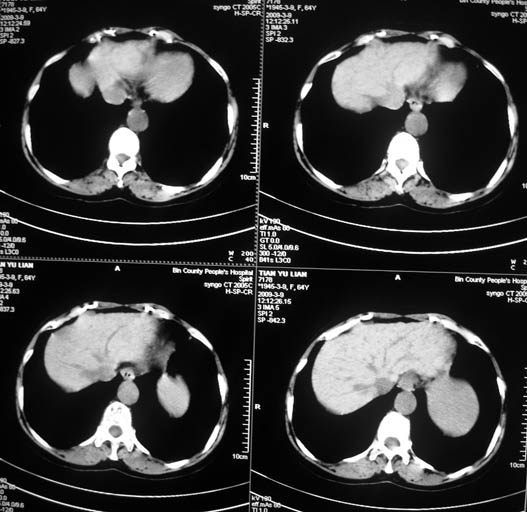

标题: CT18578:女,64岁,腹痛。 [打印本页]

标题: CT18578:女,64岁,腹痛。

女,64岁,腹痛。彩超示肝占位。

肝硬化肝癌,瘤栓?肝总管扩张。

1)肝右叶占位性病变,性质待定(不排除巨块型肝癌可能);建议行进一步检查。2)胆囊炎。3)脾大。

肝右叶占位性病变,考虑型肝癌可能!

1.肝脏形态不太规整,肝内胆管扩张,考虑有肝硬化,建议问病史。

2.肝右叶占位性病变,肝癌可能性大。

3.脾脏增大。

肝硬化肝癌,门脉右支瘤栓肝总管扩张